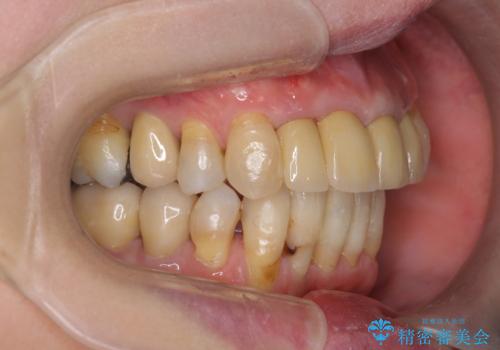

- 上顎前歯の黒ずみの改善、下顎前歯の十度なガタつき、矯正治療とセラミック治療を含む全体的な治療を希望され来院されました。

銀歯を高強度の仮歯に替えたのち、下顎前歯のみの部分矯正→全体的なマウスピース矯正治療(インビザライン)→最終的なセラミック治療と治療を進めます。

矯正治療と目立つ銀歯のやりかえを行ったことでかみあわせだけでなく、審美性・清掃性も改善し口腔内の環境を劇的に改善することができました。